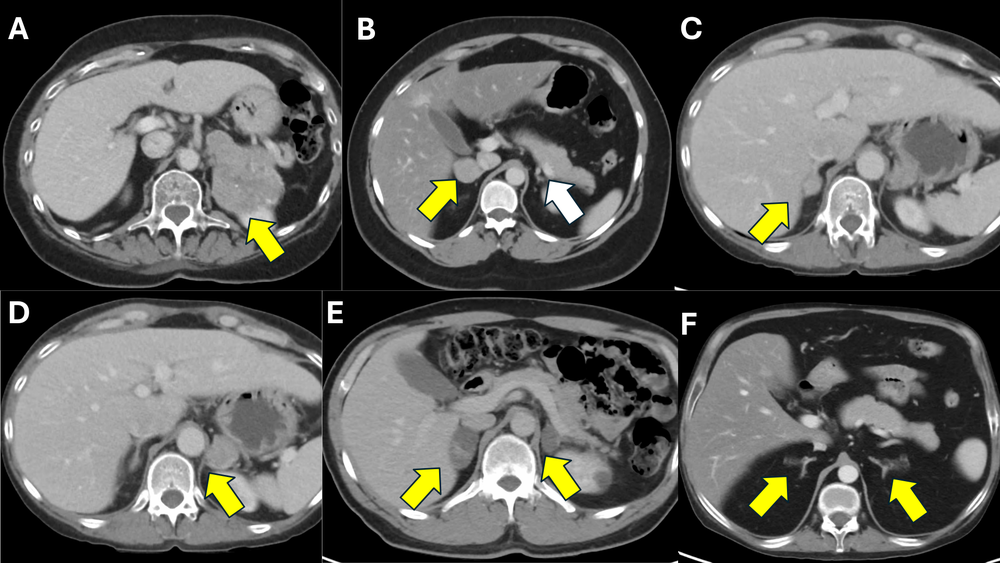

Figure 2: Representative CT scan images from patients with various subtypes of cortisol-producing adrenal lesions causing ACTH-independent Cushing’s syndrome.

A) A 70-year-old female with a large left adrenocortical carcinoma (ACC; yellow arrow), causing severe, overt adrenal Cushing’s syndrome.

B) A 25-year-old female with a right adrenocortical adenoma (yellow arrow), causing overt adrenal Cushing syndrome (CPA), with a suppressed, atrophic right adrenal gland (white arrow).

C and D) A 43-year-old female with bilateral CPAs (yellow arrows), causing overt adrenal Cushing syndrome.

E) A 49-year-old male with a bilateral macronodular adrenocortical disease (BMAD) (yellow arrows), causing subclinical Cushing syndrome (mild autonomous cortisol secretion; MACS).

F) A 31-year-old male with a bilateral micronodular adrenocortical disease (BMiNAD) (yellow arrows), causing severe, overt adrenal Cushing syndrome, in the setting of primary pigmented nodular adrenocortical disease (PPNAD).